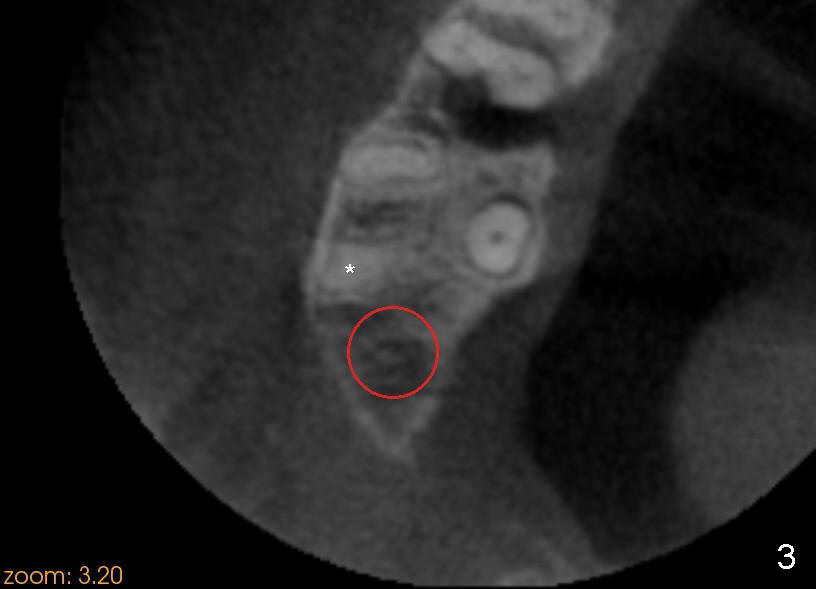

Mr. Kong is 43 years old. He has perio disease, for example #4 (Fig.1). The bone loss may be related to traumatic occlusion. The teeth #2, 14, and 15 are missing. Our primary goal is to restore these missing teeth as soon as possible. The bone height at the site of #2 is 5.8 mm. The Hounsfield units in the oral cortex, medullary and sinus floor are 400, 200 and 500, respectively. A trephine bur with outer diameter of 4 mm was used to start osteotomy (1,2). Probably due to limited access and dense bone, the trephine bur penetrated bone approximately 2 mm. A 2 mm pilot drill was used for further penetration, followed by 2.5-4.0 mm Bicon reamers for cylindrical osteotomy. A 4.5x11 mm tapered tap was used for bone expansion and sinus lift, followed by 5x11 mm tap (Fig.1). At higher magnification, it appears that the sinus floor had been lifted (Fig.1': *). A six by eleven mm tap was used. The apical end of the osteotomy felt to be intact and solid with a slender surgical curette. There was no sign of sinus membrane perforation, as confirmed by nasal blowing test. Harvested bone (from trephine bur and reamers) was pushed as apical as possible. A 6x11 mm implant was placed (Fig.2). It seems that taps/implant-related sinus lift increases the bone height to about 8 mm (Fig.2'). The thread portion of the implant is 6 mm. It appears that the 5x11 mm tap (Fig.1) and the 6x11 mm implant (Fig.2) invade the distobuccal apex of the first molar (*). Clinically there was some distance between them. Preop CT (axial section) may show the point (Fig.3: red circle stands for the implant; *: distobuccal apex of the first molar). The patient returns to office for follow up 1 week postop. The wound is healing normally around the stable implant. There is no percussion tenderness of the tooth #3. No bone resorption is observed 5.5 months postop (Fig.4), 7 months (Fig.5, Jan, 2015), 3.5 years (Fig.6) or 5 years 1 month (Fig.7) post cementation. At #14, bone height is 1-2 mm. Implant placement with sinus graft fails.